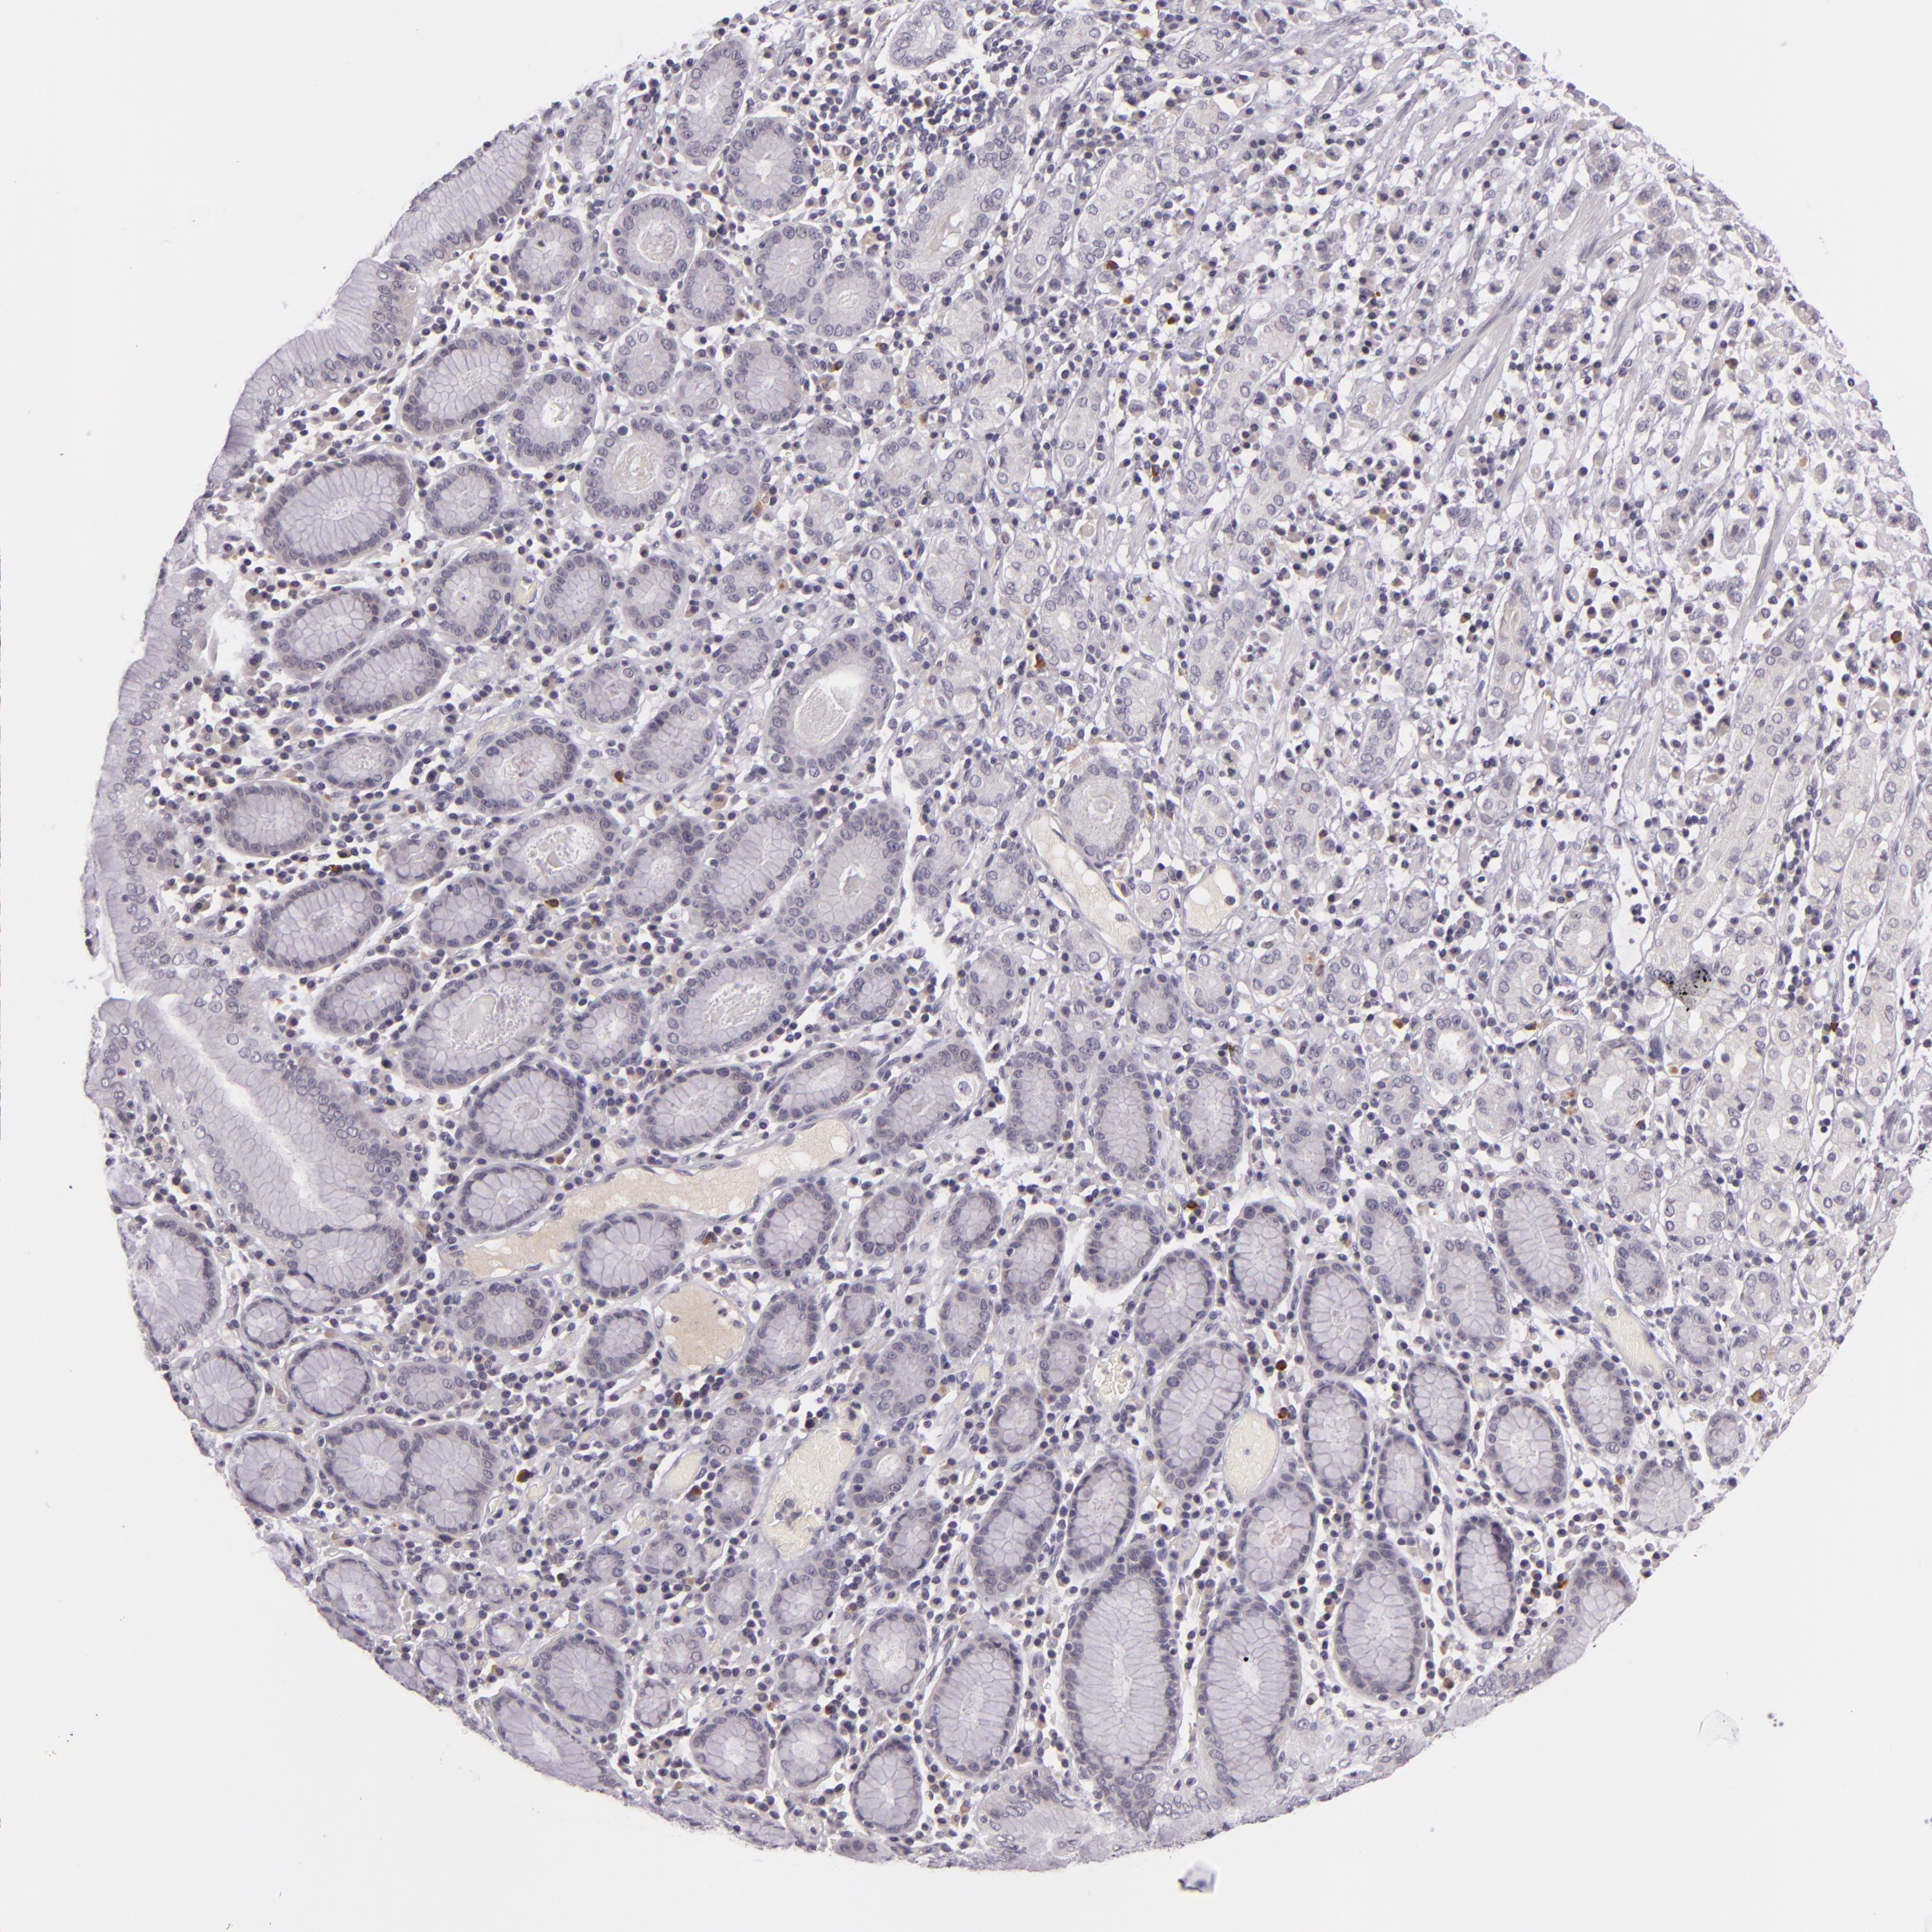

STOMACH CANCER - Protein expressioni

A mouse-over function shows sample information and annotation data. Click on an image to view it in a full screen mode. Samples can be filtered based on level of antibody staining by selecting one or several of the following categories: high, medium, low and not detected. The assay and annotation is described here.

Note that samples used for immunohistochemistry by the Human Protein Atlas do not correspond to samples in the TCGA dataset.

Antibody stainingi

Antibody staining in the annotated cell types in the current human tissue is reported as not detected, low, medium, or high, based on conventional immunohistochemistry profiling in selected tissues. This score is based on the combination of the staining intensity and fraction of stained cells.

Each image is clickable and will lead to virtual microscopy that enables deeper exploration of all samples and also displays staining intensity scores, fraction scores and subcellular localization as well as patient and tissue information for each sample.

Antibody CAB001960

Antibody CAB016353

Staining

High

Medium

Low

Not detected

Intensity

Strong

Moderate

Weak

Negative

Quantity

>75%

75%-25%

<25%

None

Location

Nuclear

Cytoplasmic/membranous

Cytoplasmic/membranous,nuclear

Adenocarcinoma, NOS

Adenocarcinoma, High grade